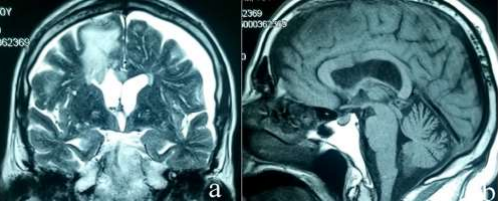

Unfortunately, two days after he consulted the emergency room. He was confused and drowsy. He had a fever without symptoms of meningitis. The MRI showed a good tumoral resection without any features of complications. (Figure 2)

Figure 2: Postoperative MRI: a; T2 coronal showing a total resection and liberation of the flow through the interventricular foramina. we can notice postoperative frontal edema without signal abnormalities of the hypothalamus.b- sagittal T1 showing the good status of the structures around the third ventricle without features of complication